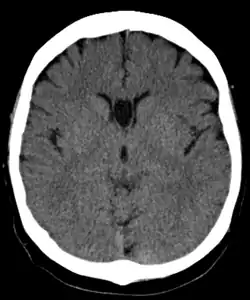

The cave of septum pellucidum (CSP), cavum septi pellucidi, or cavity of septum pellucidum, also known as the ventricle of Sylvius, is a slit-like space in the septum pellucidum that is present in fetuses but usually fuses during infancy.[1] The septum pellucidum is a thin, laminated translucent vertical membrane in the midline of the brain separating the anterior horns of the right and left lateral ventricles. It lies posterior to the corpus callosum. Persistence of the cave of septum pellucidum after infancy has been loosely associated with neural maldevelopment and several mental disorders that correlate with decreased brain tissue.[2][3][4][5][6]

The cave of septum pellucidum is bounded anteriorly by the genu of the corpus callosum, superiorly by the body of the corpus callosum, posteriorly by the anterior limb and pillars of the fornix, inferiorly by the anterior commissure and the rostrum of the corpus callosum, and laterally by the leaflets of the septum pellucidum.[7]

There are individual differences in the degree of CSP; whereas some have complete closure of the cavum, others present with a small degree (4–6 mm wide, in the coronal plane) of incomplete closure.[5] The most common type of CSP is noncommunicating; that is, it does not connect to the brain's ventricular system. Because of this lack of communication, the previous use of the term "fifth ventricle" is no longer used, and the fifth ventricle is the name often used for the terminal ventricle.